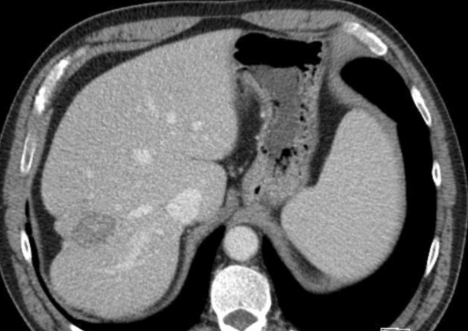

肝硬化中的纤维化较大范围集中时称为融合性纤维化,多见于进展期肝硬化,主要见于酒精性肝硬化。融合性纤维化形态上分为斑片状和肿块状,而肿块状病灶可能为误诊为恶性。CT 上表现为低密度,常累及肝左内叶和右前叶,而尾状叶较少累及。由于纤维组织收缩牵拉,邻近肝体积缩小,肝包膜凹陷(见于 90% 融合性纤维化中),病灶内胆管亦可扩张。MRI 上表现为 T1WI 低信号、T2WI 高信号,信号均匀,增强后呈动脉期无或轻度强化,后呈持续性强化。

肝融合性纤维化,肝硬化背景,增强后肝 S4 段相对稍低密度,邻近肝包膜凹陷。